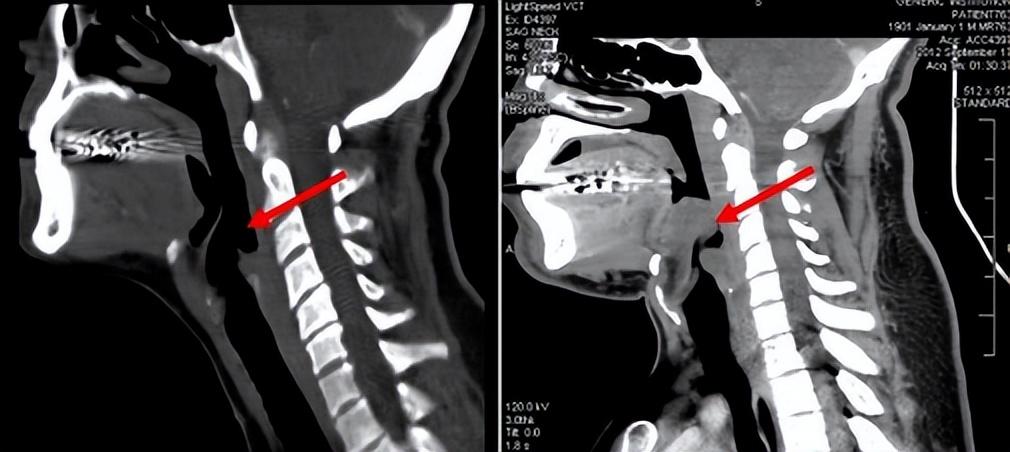

會厭處於舌根後方,一般我們進食時食物會經過咀嚼形成球狀,此時會厭自動關閉,防止食物進入肺部。可一旦會厭發炎,就可能堵塞呼吸道,這時就會呼吸困難。

一般,急性會厭炎的病情進展十分迅速,一旦發病後沒有及時診療,可在極短時間內窒息,因此死亡率較高。